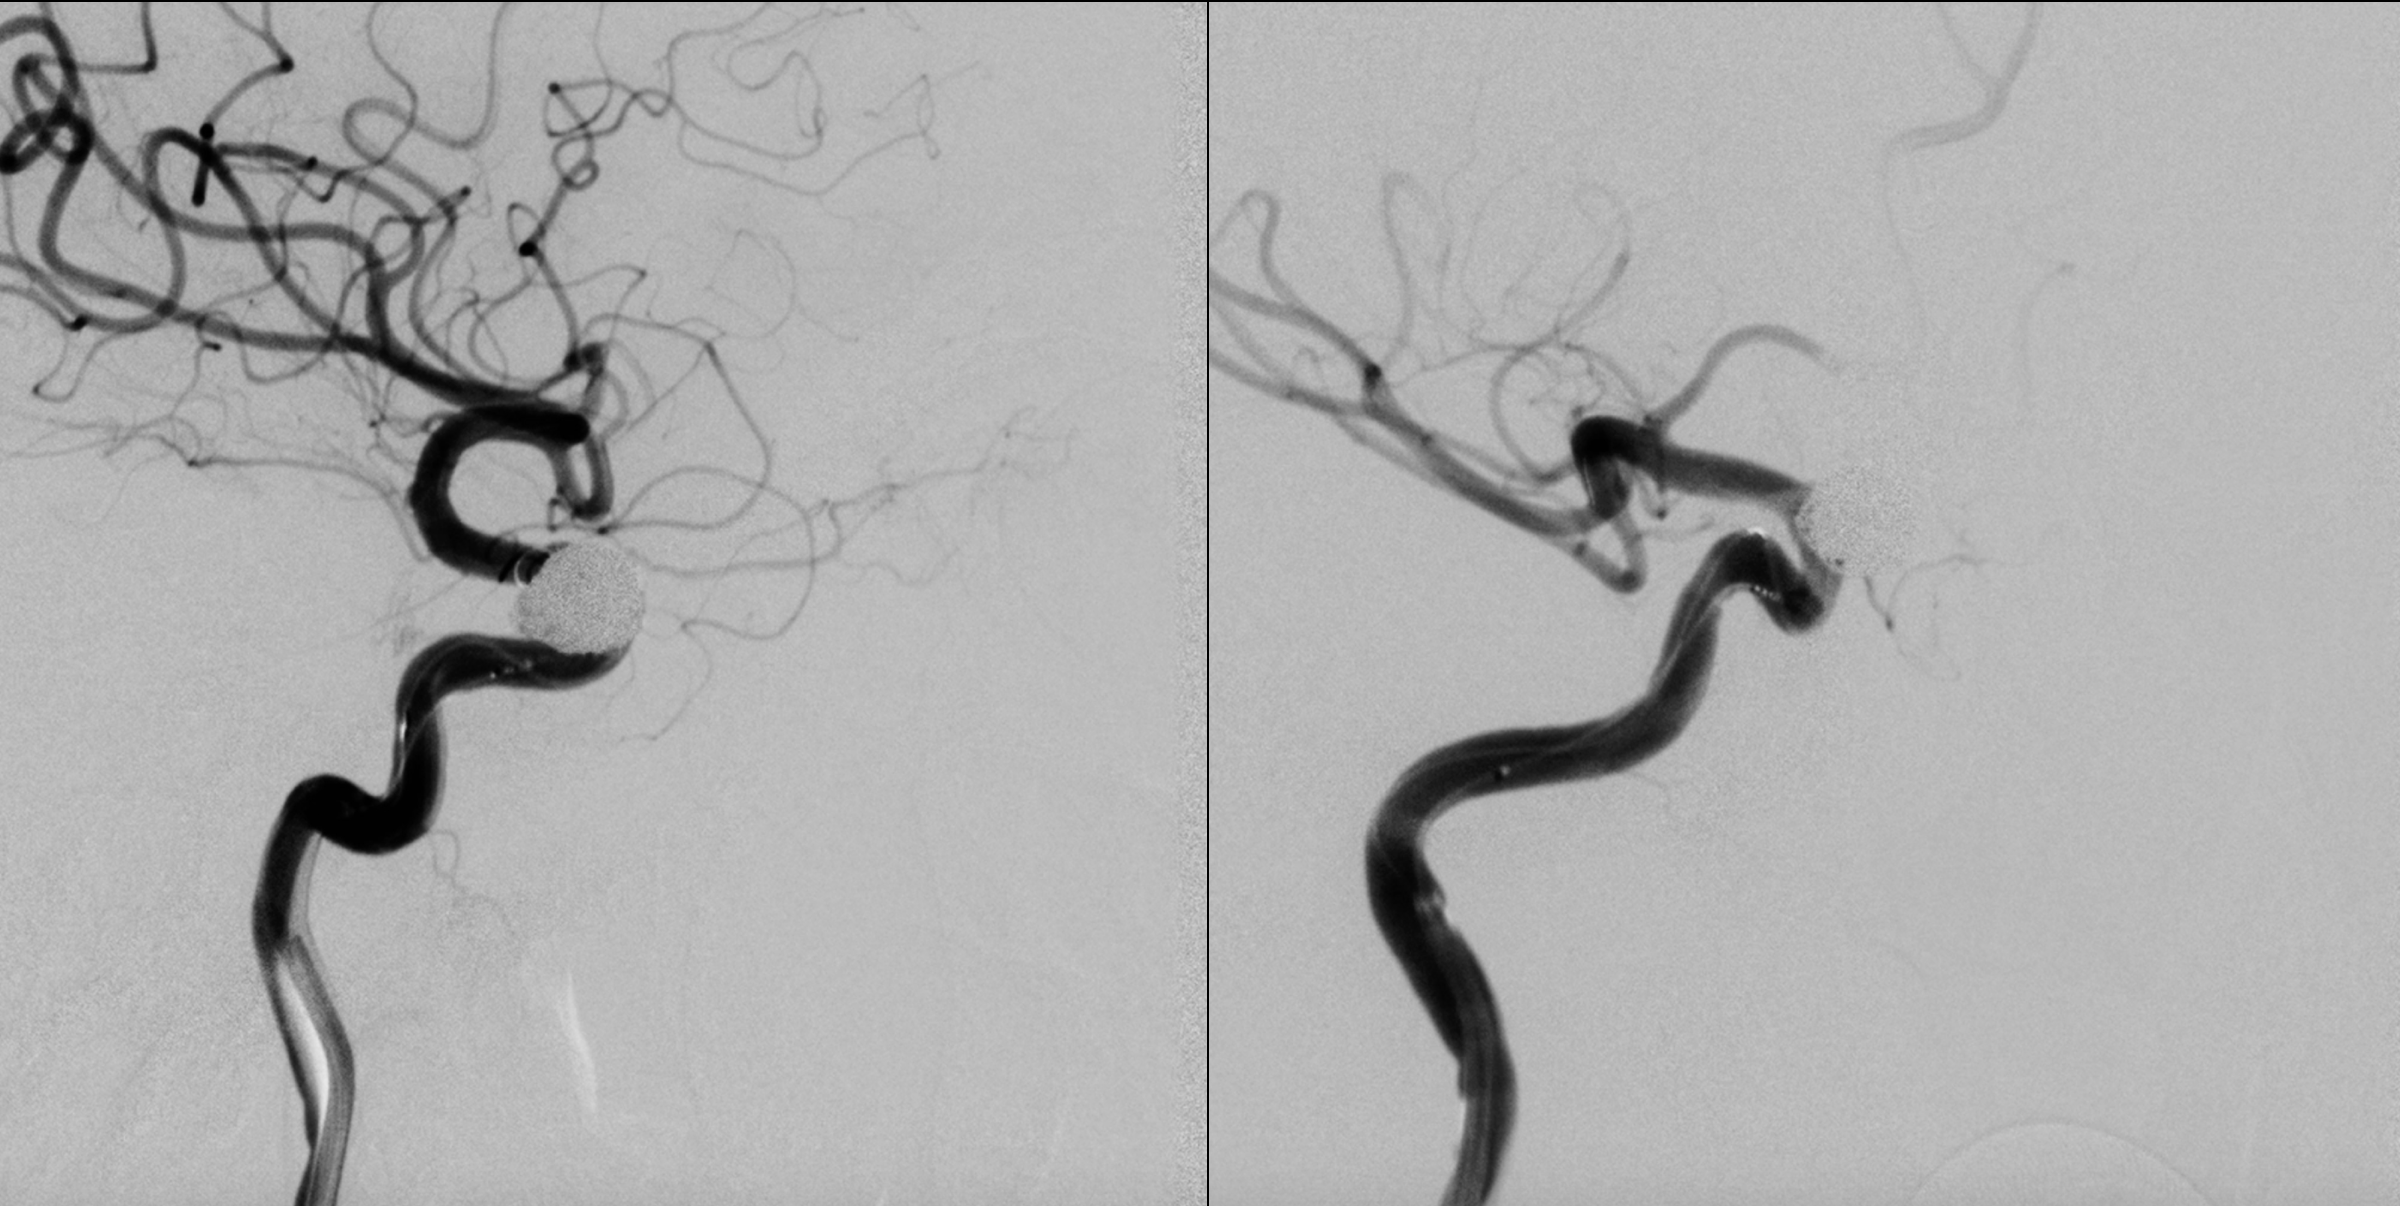

右侧颈内动脉正侧位造影:眼动脉段动脉瘤。

右侧颈内动脉三位造影重建:眼动脉段动脉瘤。给予支架辅助栓塞治疗。